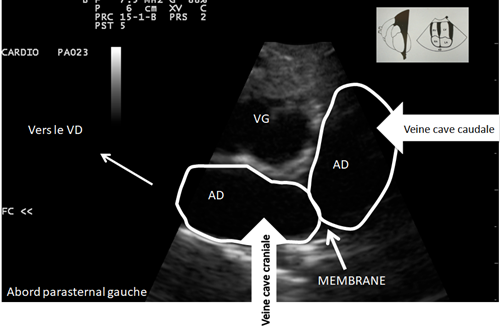

On a une sensation de bombement a certains endroits de l’AD

Bilan échocardiographique

- Confirmation de l’hypothèse de

Cor triatriatum dexter

Le CTD est due à la persistance d’une membrane fibreuse au sein de l’AD, cette membrane est probablement le résidu d’une valve du sinus veineux.

Il existe de nombreuses variantes du CDT selon la position de la membrane par rapport aux coronaires….

Du fait de la présence de cette membrane dont l’ouverture peut être plus ou moins grande, le retour veineux est compromis.